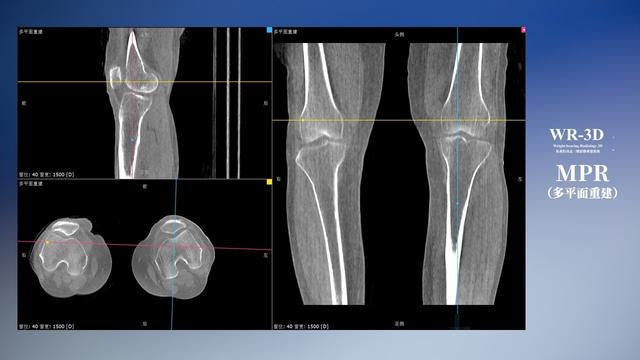

普通平片掃描與WR-3D掃描前后診斷結果對比

與此同時,數字化X線攝影技術相較于CTMRI來說,能快速獲取真實、直觀、滿足臨床需要的影像。DR的圖像具有圖像層次豐富、空間分辨力高、影像邊緣銳利清晰、密度分辨力高級細微結構表現出色等特點,針對膝關節解剖結構數字化X線攝影技術應用價值很高,尤其是是對骨小梁與骨皮質的顯示非常清楚。在負重位狀態下,數字化X線三維攝影掃描與重建,能夠更好的呈現受檢者關節受力改變的狀態。安健科技創新的WR-3D動態三維數字化X線攝影技術,通過數字化X線攝影完成三維掃描并重建三維影像信息,包括MPR多平面重建、MIP重建以及VR繪制。掃描時間短,劑量相較于CT設備大幅縮減,同時成本更低,在臨床診斷以及醫療方案制定中具有極大的價值意義。相較于普通平片下的負重位掃描,負重位動態三維掃描攝影技術能夠避免二維狀態下的組織結構重疊、密度分辨率不足、組織解剖結構難以分辨等問題,WR-3D支持多角度的動態三維攝影觀察,能全面的呈現被檢查部位在多個角度下三維影像信息,極大的減少了二維負重位檢查的漏診率。

安健科技WR-3D負重位動態三維攝影技術